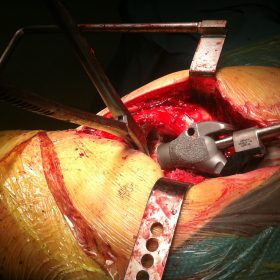

Διατροχαντήριο : Εξωαρθρικό κάταγμα, στην περιοχή ανάμεσα στο ελάσσονα και το μείζονα τροχαντήρα. Αντιμετωπίζεται χειρουργικά με ενδομυελική ήλωση τύπου γ-Nail. Δύο τομές 3 εκατοστών και 1 εκατοστού αντιστοίχως για την εισαγωγή και το κλείδωμα του ήλου μέσα στο οστό. Η μέθοδος είναι κλειστή,σχεδόν αναίμακτη,διάρκειας 30 λεπτών,με τη βοήθεια C-ARM (τηλεόρασης). Στον ασθενή παρέχεται οπτικό υλικό (όλα τα χειρουργικά στάδια) σε CD ή Στικάκι,λόγω της δυνατότητας καταγραφής του χειρουργείου από το C-ARM Ο ασθενής περπατάει άμεσα μετεγχειρητικά στις 5 ώρες μετά την επέμβαση και εξέρχεται από το νοσοκομείο σε 1 -2 ημέρες.

Υποτροχαντήριο :Εξωαρθρικό κάταγμα κάτω από τον ελάσσονα τροχαντήρα του μηριαίου οστού. Αντιμετωπίζεται χειρουργικά με ενδομυελική ήλωση τύπου Long γ-Nail. Δύο τομές 3 εκατοστών και 1 εκατοστού αντιστοίχως για την εισαγωγή και το κλείδωμα του ήλου μέσα στο οστό. Η μέθοδος είναι κλειστή,σχεδόν αναίμακτη,διάρκειας 60 λεπτών,με τη βοήθεια C-ARM (τηλεόρασης). Στον ασθενή παρέχεται οπτικό υλικό (όλα τα χειρουργικά στάδια) σε CD ή Στικάκι,λόγω της δυνατότητας καταγραφής του χειρουργείου από το C-ARM Ο ασθενής περπατάει άμεσα μετεγχειρητικά στις 5 ώρες μετά την επέμβαση και εξέρχεται από το νοσοκομείο σε 1 -2 ημέρες.